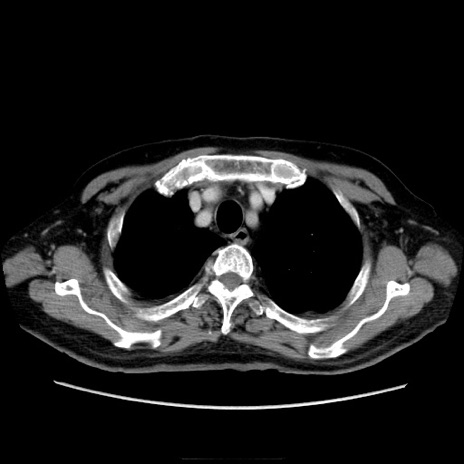

冠状断像

症例21(横断像)

【症例】70歳代男性

【現病歴】肝硬変・肝細胞癌にてかかりつけの方。約9時間前に食後より腹痛出現。症状が徐々に増悪し、嘔吐出現したため来院。

【既往歴】肝硬変、肝細胞癌(RFA、TACE後)